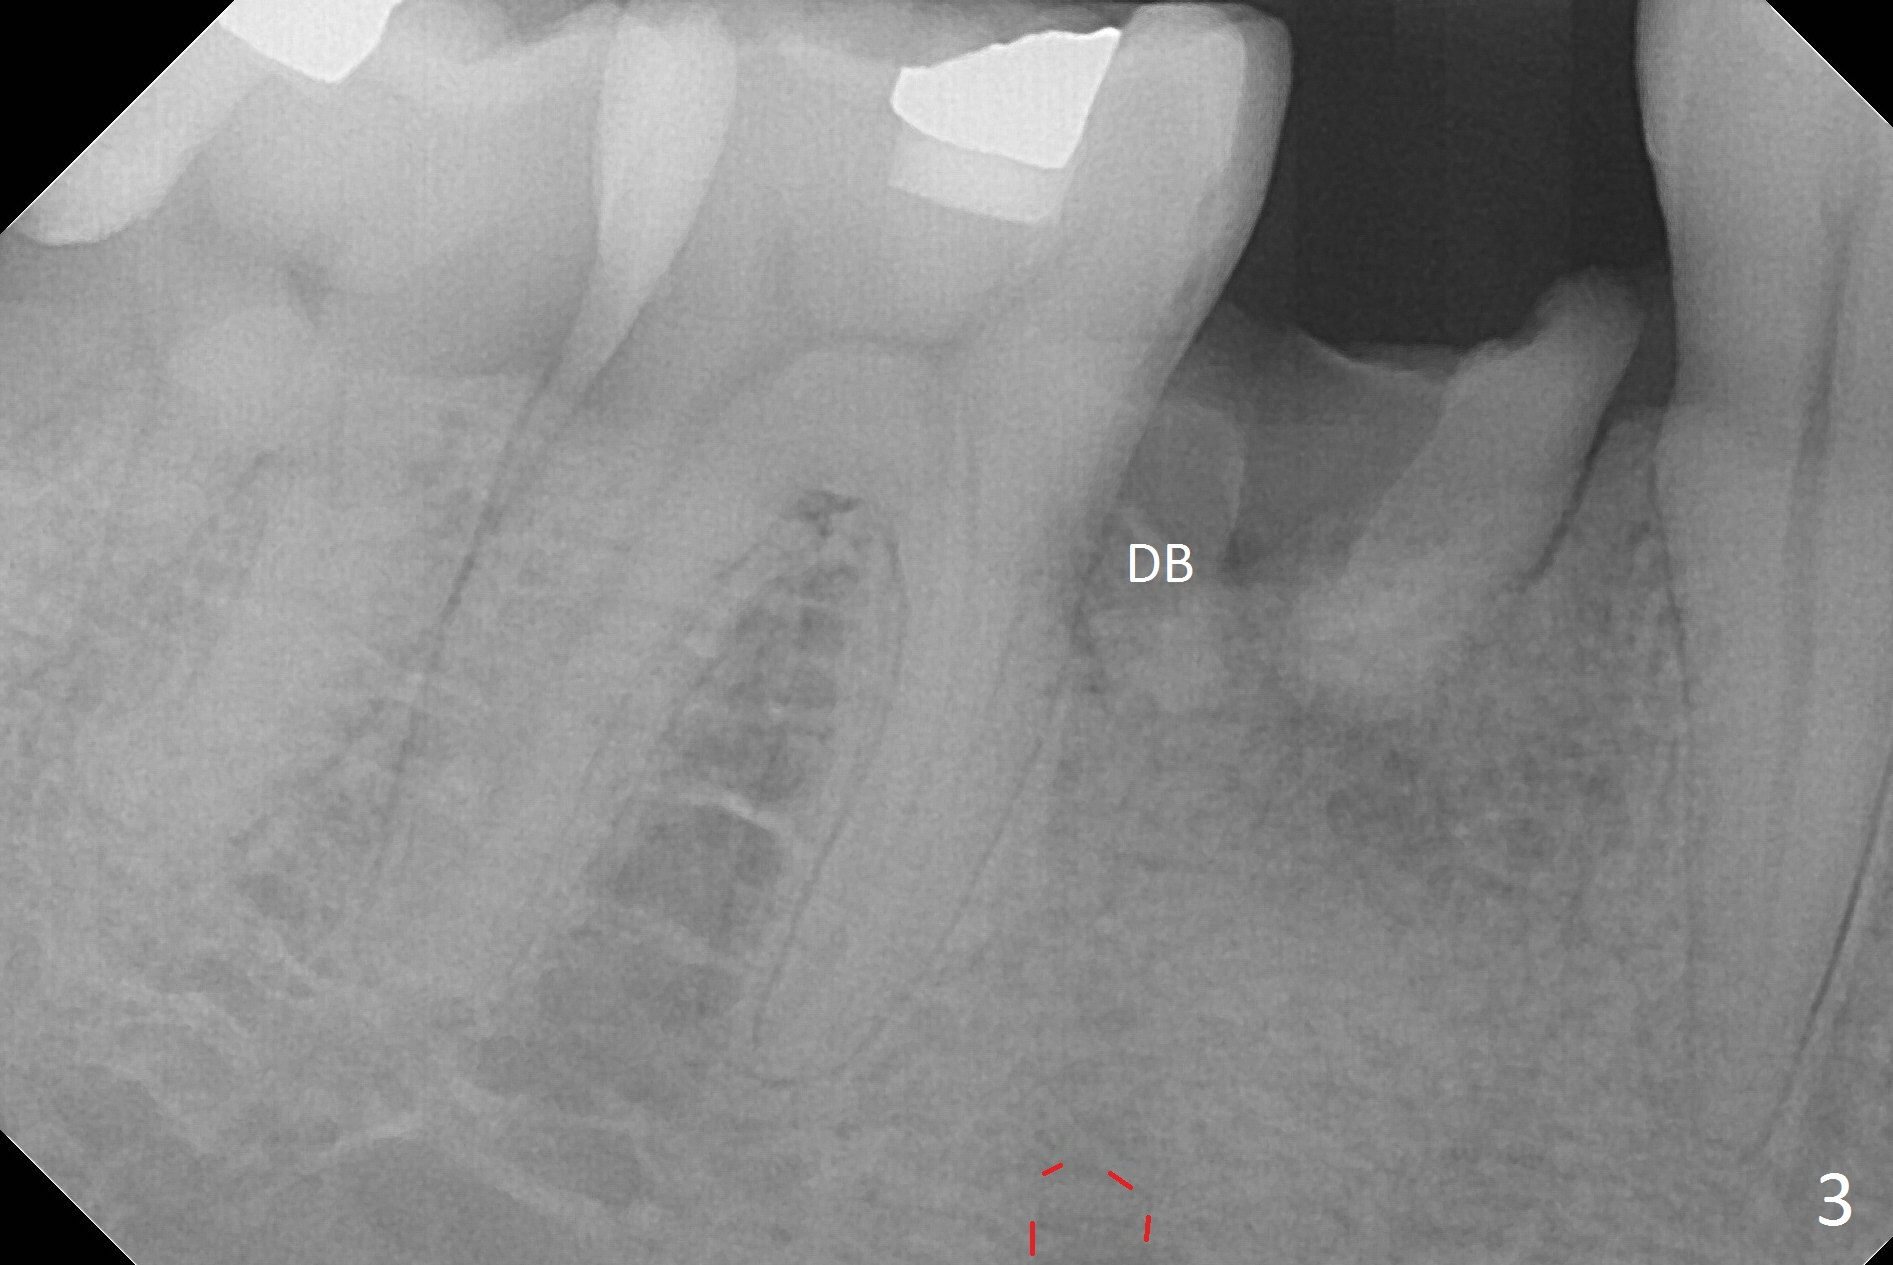

When a 46-year-old man presents with new patient examination, the tooth #29 has root fracture with a crown in place (Fig.1). A year later when he returns for #32 extraction, the crown is lost with displacement of the distobuccal (Fig.2,3 DB) portion of the root. The gingival recession is severe. When the root is removed, an implant will be placed as lingual as possible (Fig.5 white circle). Magic Drill 3.3 mm will be used for osteotomy (without 1.6 mm drill). Trajectory and depth will be tightly controlled while starting and advancing the drilling (one shot). Take PA following partially inserting a 4x11 mm dummy implant.